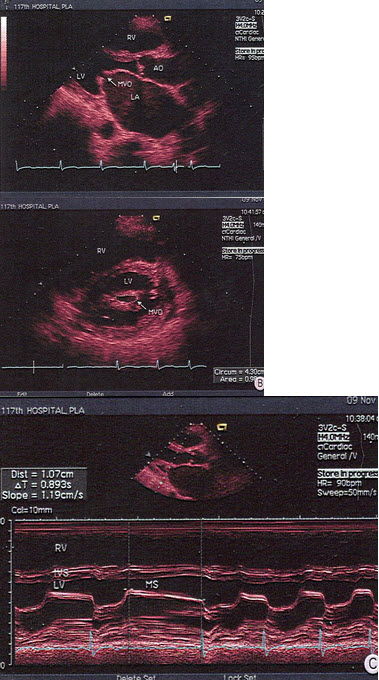

53、单项选择题

该病例最有可能诊断是()

A.原发孔房缺

B.继发孔房缺

C.冠状静脉窦隔缺损

D.部分性肺静脉畸形引流

E.部分型心内膜垫缺损

125、单项选择题

某患者舒张期二尖瓣口心动图所示,提示()

A.二尖瓣狭窄

B.二尖瓣关闭不全

C.二尖瓣脱垂

D.正常声像图

E.二尖瓣赘生物